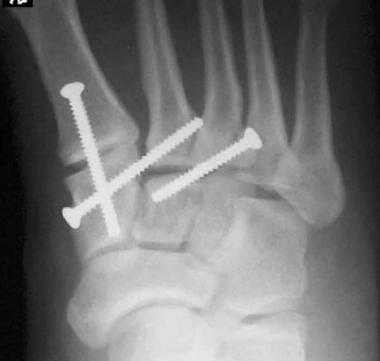

При смещении более 2 мм, нестабильности при функциональных тестах - рекомендовано открытое устранение вывиха с жёсткой фиксацией винтами или пластинами. Используются один или два продольных доступа в 1 и 2 межплюсневых промежутках. После обнажения первого предплюсне-плюсневого сустава первым этапом устраняется межклиновидная нестабильность, вторым этапом устраняется предплюсне-плюсневая нестабильность. В послеоперационном периоде сразу начинается разработка активного объёма движений. Нагрузку на стопу начинают постепенно, с тем чтобы полностью её восстановить к 6-8 неделе. Удаление спиц Киршнера производится через 6-8 недель, компрессирующих винтов через 3-6 месяцев. Возвращение к полной физической активности не ранее 9-12 месяцев после операции.

Открытое вправление вывиха, трансартикулярная фиксация 1-2-3 предплюсне-плюсневых суставов винтами.

В случаях этого повреждения показано оперативное лечение, открытое устранение подвывиха основания 2 плюсневой кости с фиксацией винтом. Устранение подвывиха производится из доступа в 1 межплюсневом промежутке, рубцовая ткань и остатки связки могут интерпонировать сустав, тогда потребуется их удалить. После вправления производится предварительная фиксация спицей и рентгенологический контроль.

Затем устанавливается винт соединяющий основание 2 плюсневой кости и медиальную клиновидную кость.